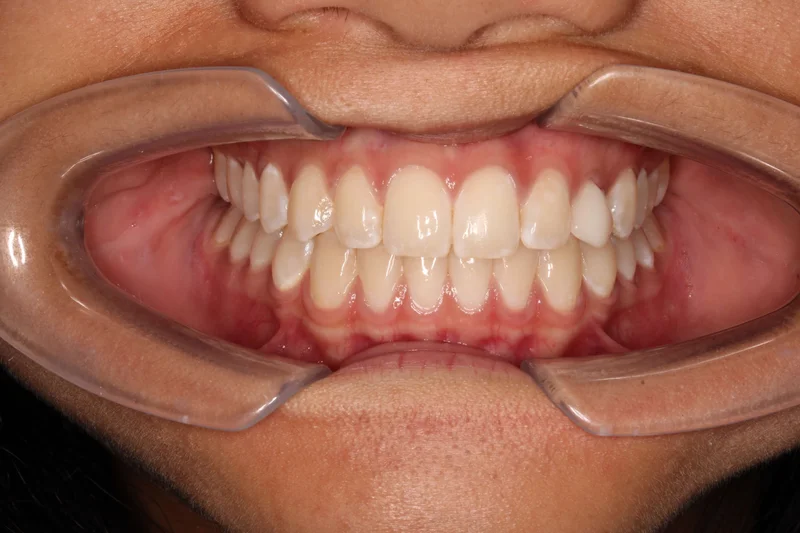

Center Closed

Center Closed - Before Treatment

Before

Center Closed - After Treatment

After